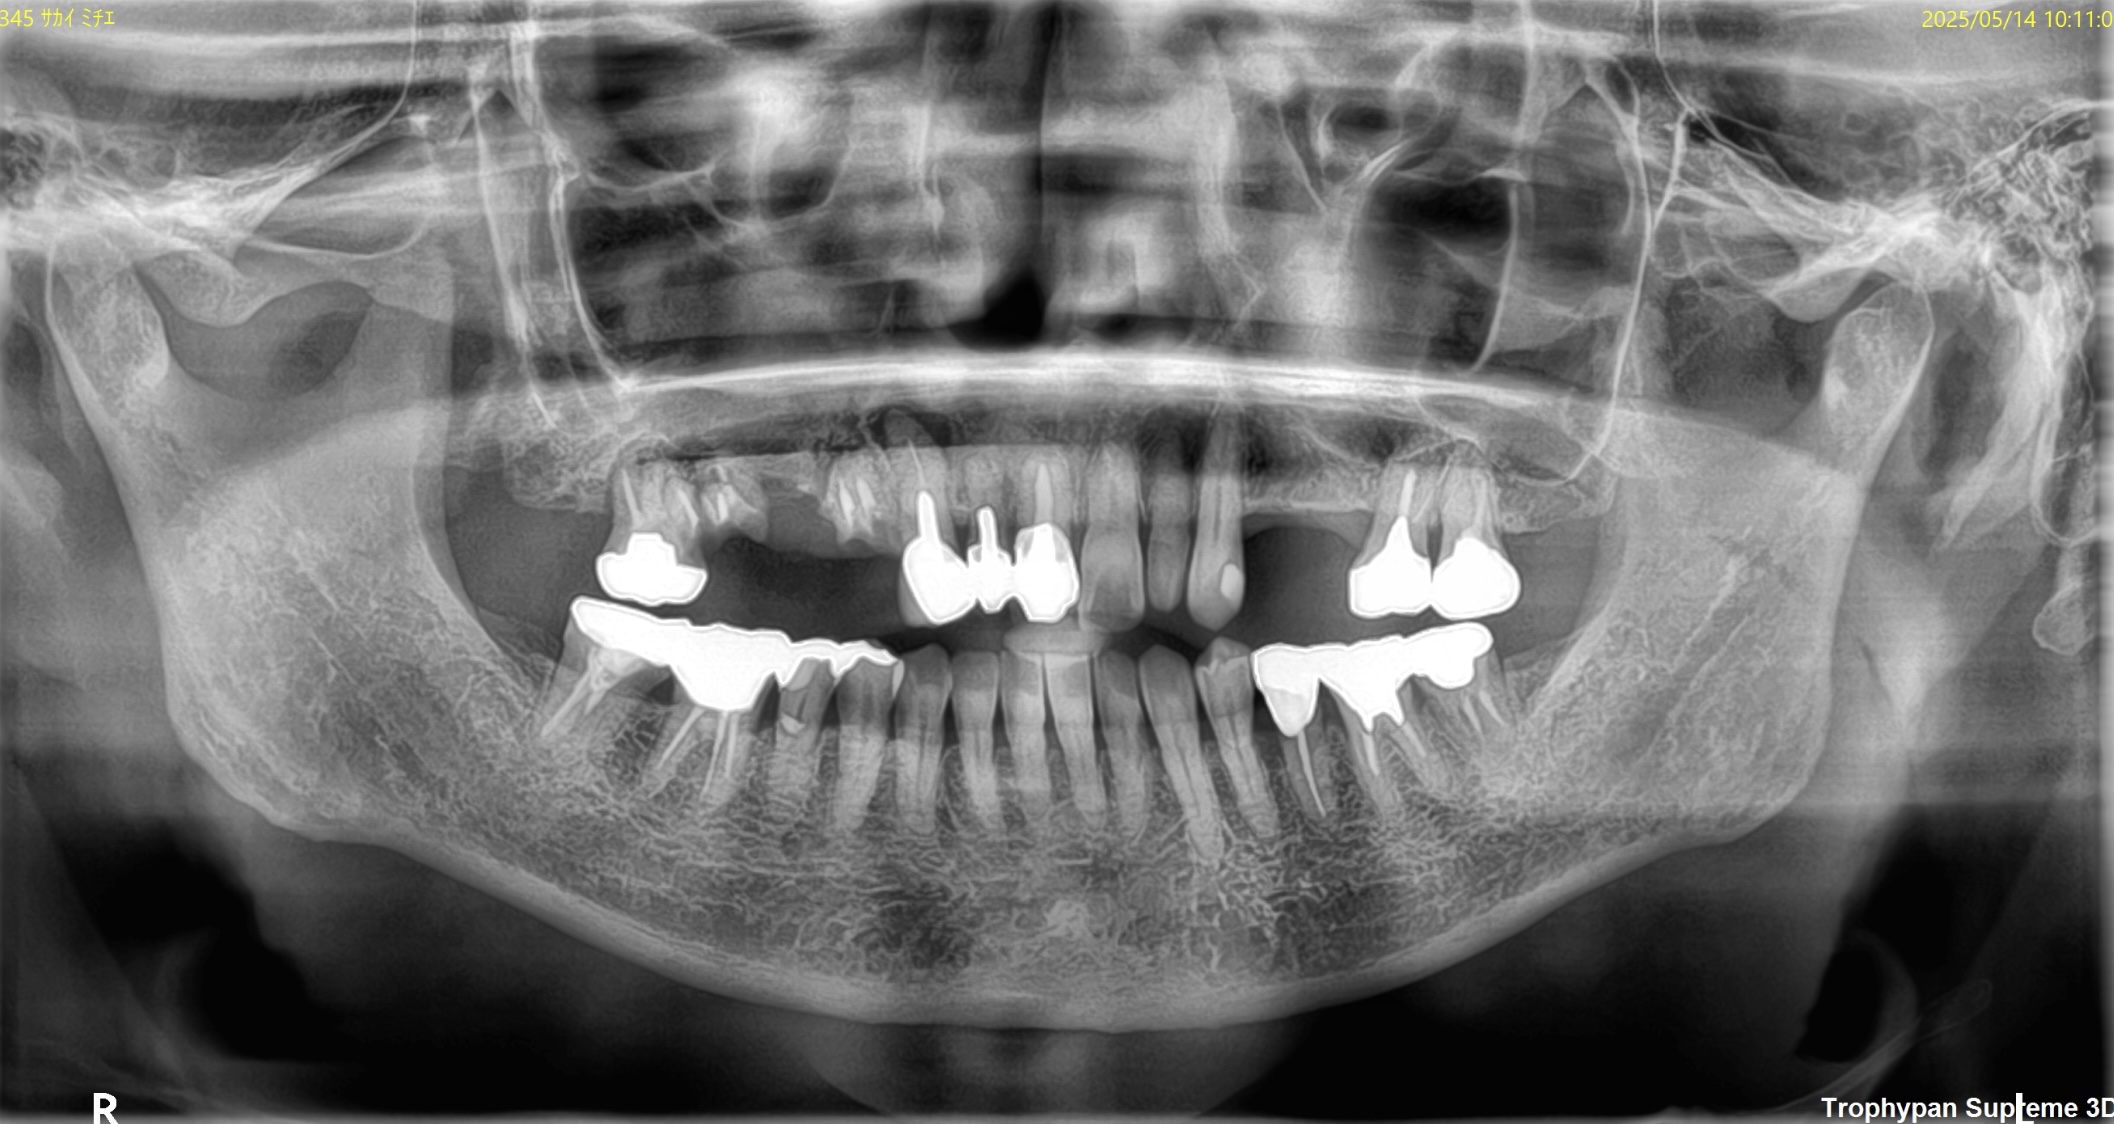

CASE

1